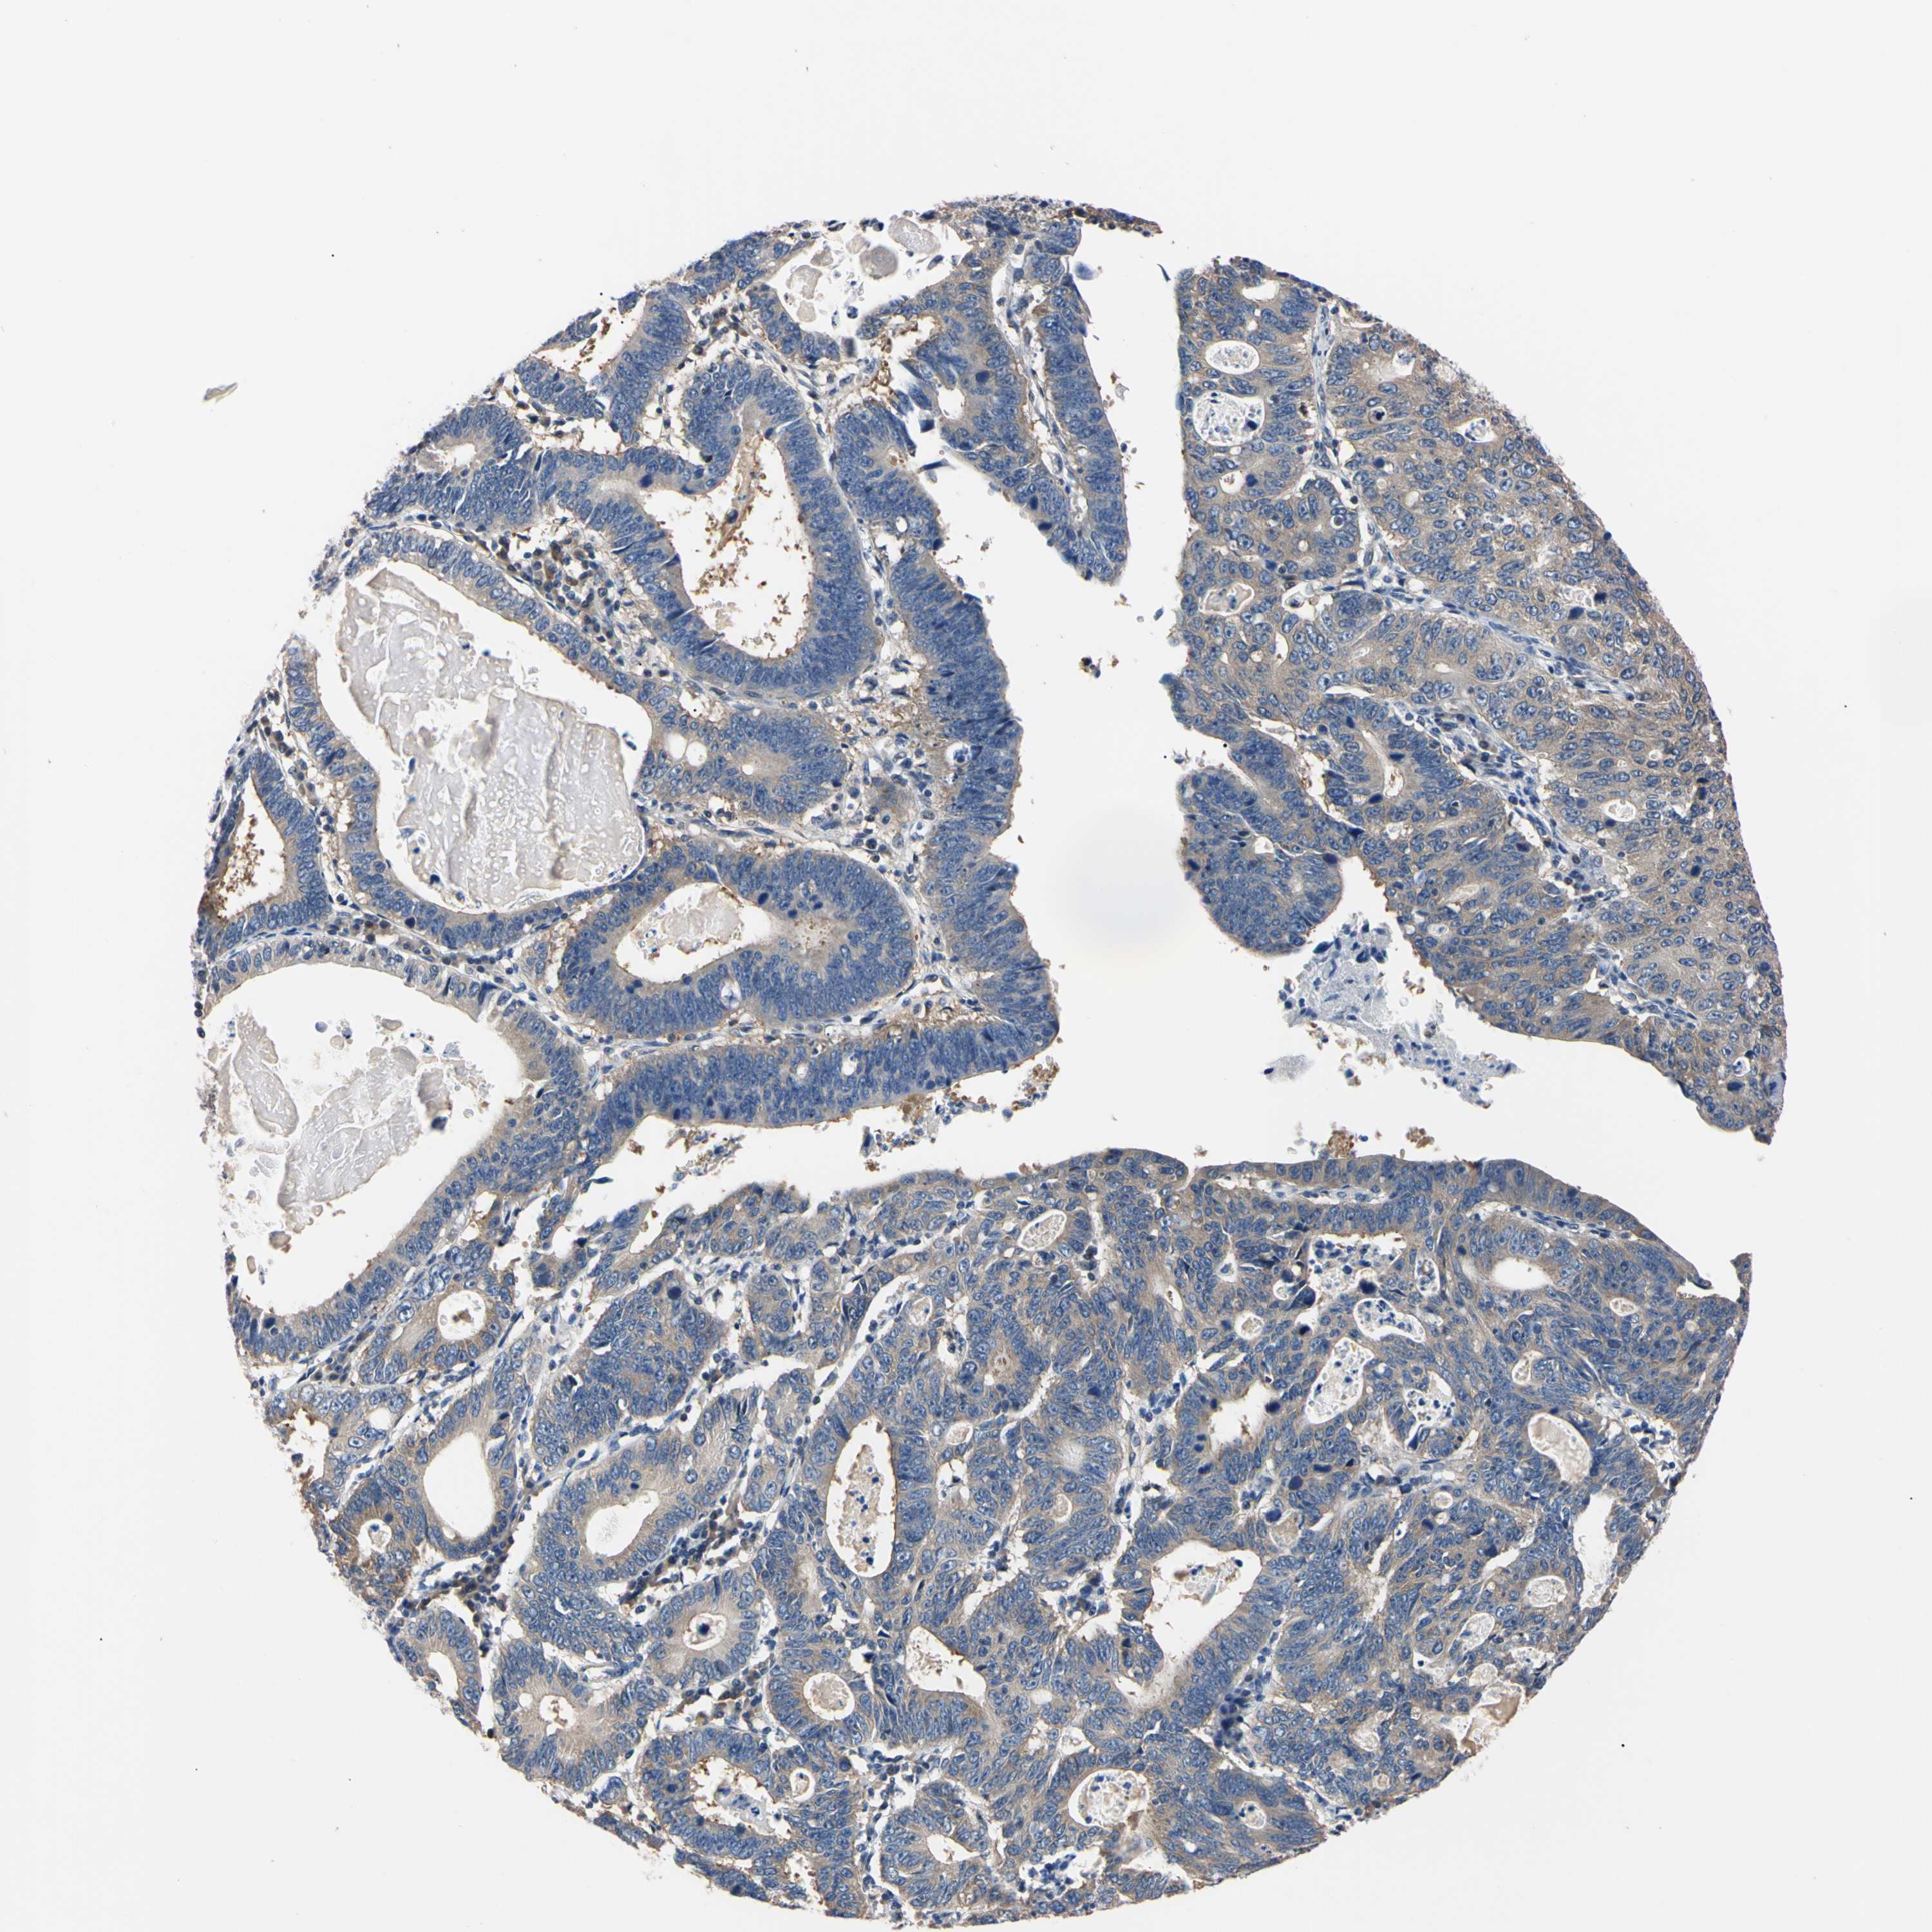

STOMACH CANCER - Protein expressioni

A mouse-over function shows sample information and annotation data. Click on an image to view it in a full screen mode. Samples can be filtered based on level of antibody staining by selecting one or several of the following categories: high, medium, low and not detected. The assay and annotation is described here.

Note that samples used for immunohistochemistry by the Human Protein Atlas do not correspond to samples in the TCGA dataset.

Antibody stainingi

Antibody staining in the annotated cell types in the current human tissue is reported as not detected, low, medium, or high, based on conventional immunohistochemistry profiling in selected tissues. This score is based on the combination of the staining intensity and fraction of stained cells.

Each image is clickable and will lead to virtual microscopy that enables deeper exploration of all samples and also displays staining intensity scores, fraction scores and subcellular localization as well as patient and tissue information for each sample.

Antibody HPA003979

Antibody HPA004130

Staining

High

Medium

Low

Not detected

Intensity

Strong

Moderate

Weak

Negative

Quantity

>75%

75%-25%

<25%

None

Location

Nuclear

Cytoplasmic/membranous

Cytoplasmic/membranous,nuclear

Adenocarcinoma, NOS

Adenocarcinoma, High grade